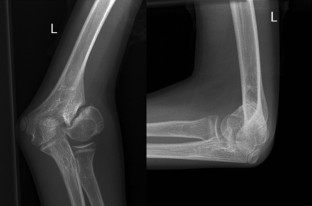

Die Pseudarthrose des kindlichen Condylus radialis humeri mit posttraumatischem Cubitus valgus stellt nach inadäquater Behandlung eine ernsthafte Komplikation dar. Wir berichten über einen damals 14-jährigen männlichen Patienten, der nach konservativer Frakturbehandlung des Condylus radialis humeri eine zunehmende Fehlstellung im Sinne eines Cubitus valgus entwickelte. Nach Durchführung einer Schraubenosteosynthese wurde nach gesicherter Konsolidierung eine erfolgreiche suprakondyläre Domosteotomie vorgenommen, die zur Beschwerdefreiheit und freien Beweglichkeit des Ellenbogengelenks führte.

Non-union of the pediatric lateral humeral condyle following post-traumatic cubitus valgus is a severe complication after inadequate treatment. We report on a then 14-year-old male patient who developed an increasingly defective position in terms of cubitus valgus after conservative treatment of a lateral humeral condyle fracture. After performing screw osteosynthesis and achieving consolidation, a successful supracondylar dome osteotomy was performed which led to relief from pain and free range of motion of the elbow joint.

Abb. 1